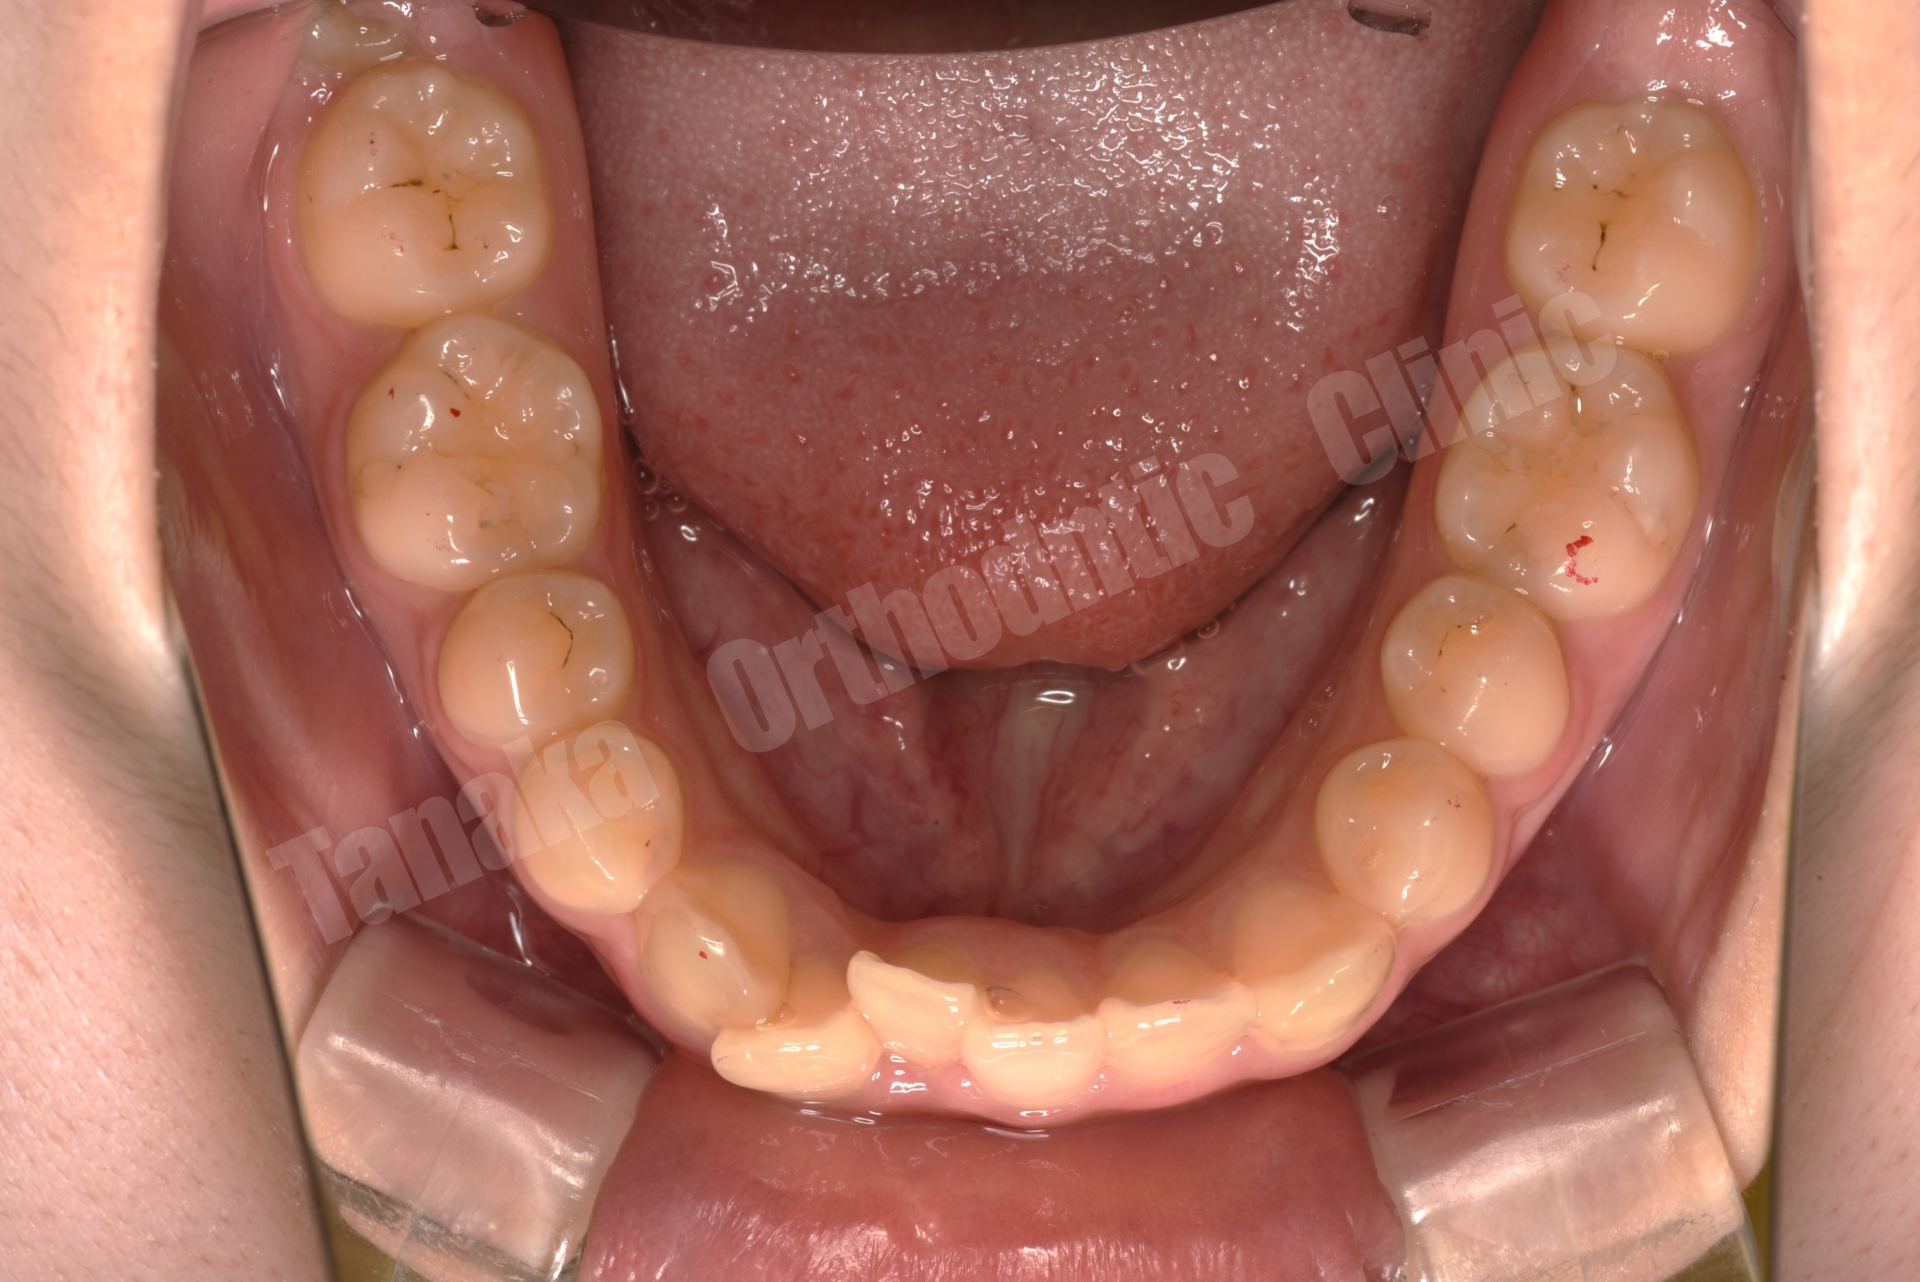

| 主訴 | 八重歯(13.23)、上顎正中の右偏位、下顎前歯のガタガタ |

| 診断 | 下顎前突(上顎後退傾向&下顎前突傾向)、上下顎歯列の叢生(上顎右側3番完全唇側転位&上顎正中の右偏位)、上下左右8番を認める |

上下顎叢生(13完全唇側転位)